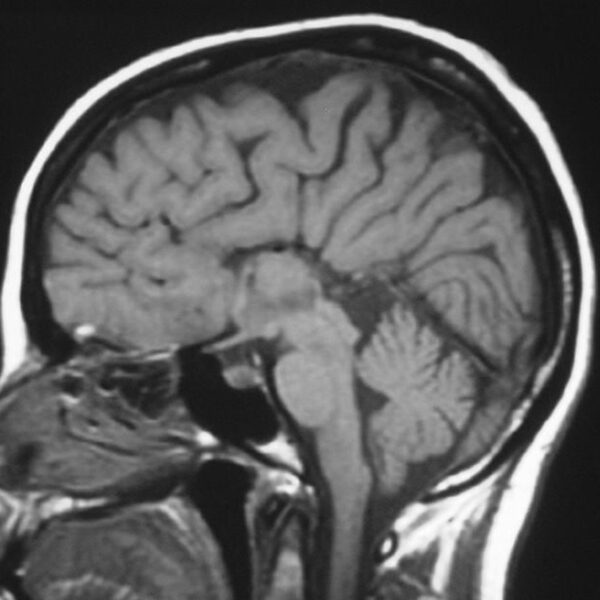

MRI

Showing 1–9 of 86 results